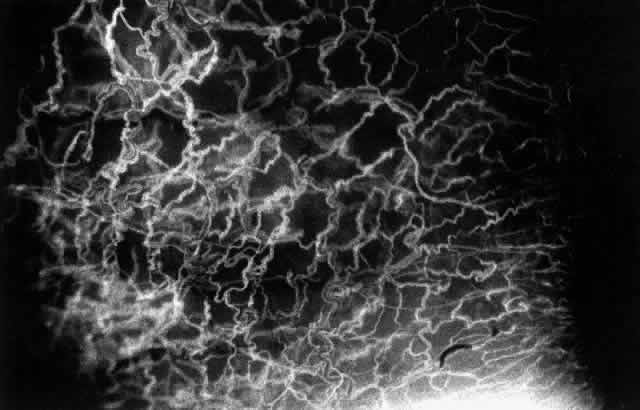

With the increasing use of anterior segment fluorescein angiography in the early detection of severe necrotizing disease of the sclera, it is necessary to have an understanding of the normal anatomy of the vasculature of the anterior segment of the eye.3–5 The blood supply to this region is enormous, being derived from the anterior ciliary arteries, but with extensive collateral arterial anastomoses to the posterior ciliary arteries at the root of the iris (Fig. 1). The anterior system is readily visible with the slit lamp and by anterior segment fluorescein angiography, especially if the eye is inflamed, and its recognition is of vital importance in the differentiation of episcleral and scleral conditions. The separation and displacement of these vascular layers give the most important clinical clues to the site and, hence, the severity of the inflammation. On slit lamp examination, three layers of vessels are readily visible. The conjunctival plexus, which is the most superficial layer of vessels, can be moved over the underlying structures. The superficial episcleral capillary plexus (Fig. 2) is a radially arranged series of vessels lying within the parietal layer of Tenon's capsule. The vessels in this layer anastomose at the limbus with the conjunctival vessels, with other members of the same plexus, and with the deep plexus. The deep episcleral capillary network (see Fig. 2) is closely applied to the sclera in the visceral layer of Tenon's capsule. The vessels anastomose freely with each other, forming a syncytium. The large vessels to and from the intrascleral plexus traverse the episclera near the insertions of the muscles. The conjunctival and superficial episcleral vessels can be blanched with 1:1000 epinephrine or 10% phenylephrine, but the deep vessels are affected slightly. This is of considerable assistance when attempting to differentiate deep and superficial inflammation.

Fig. 1. Anterior view montage of a cynomolgus monkey ocular casting with Tenon's and episcleral vessels removed. The anterior ciliary arteries (ACA) arborize at the limbus and interconnect via their lateral branches to form the episcleral circle. (CM, ciliary muscle capillary bed; CV, choroidal veins; EC, episcleral circle. (Original magnification, X20). (Morrison JC, van Buskirk EM: Anterior collateral circulation in the primate eye. Ophthalmology 90:707, 1983)

Fig. 2. The normal relationships of the capillary networks that can be seen with the slit lamp are a conjunctival (easily mobile) network, a superficial episcleral network in the parietal layer of Tenon's capsule, and a deep episcleral plexus closely applied to the sclera. These relationships are much more obvious in inflamed eyes (see Figs. 13, 14, and 30). (Watson PG, Hayreh S, Awdry P: Episcleritis and scleritis. Br J Ophthalmol 52(3):278– 279, 1968)